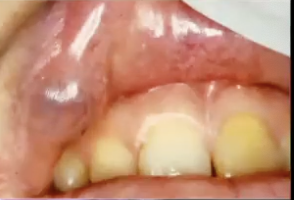

<p>What is the diagnosis?</p>

What is the diagnosis?

Mucocele